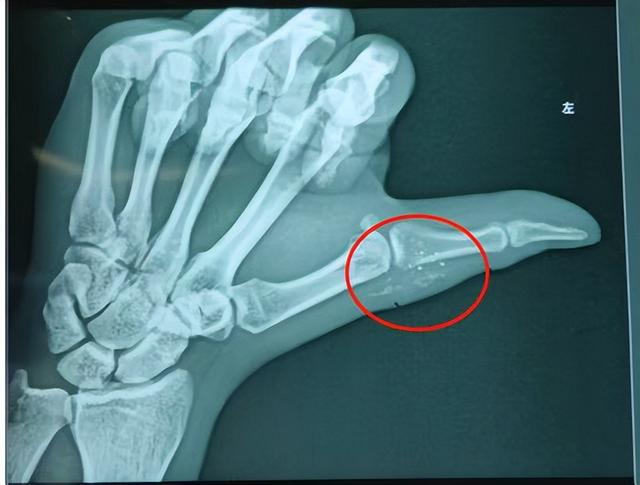

一个多月前 , 36岁的周先生(化姓)正在家测量体温 。 甩体温计时不慎打碎了水银体温计 。 当时破碎的玻璃渣刺破了左手拇指 , 留下感觉不起眼的小伤口 。 据周先生回忆 , “当时想过会不会有水银弄进去了 , 但是看着伤口这么小 , 就没有在意” , 周先生说 , 当时他简单挤压了伤口 , 随后清理了地板上玻璃渣、水银 , 就没有进一步处理拇指上的伤口 。 然而20多天后 , 周先生发现当初受伤的地方肿痛难忍 , 于是到附近医院检查 。 X线片显示周先生左手拇指近节指骨有广泛散在的星星状致密影 , 怀疑是残留在手部软组织中的水银 。 当地医生建议周先生立刻前往骨科专科就诊 , 做进一步的处理 。 然而工作繁忙请假困难的周先生仍未重视 , 再次等待10天后 , 症状加重后周先生来到武汉市第四医院就诊 。

该院手外科吴其鹏医生接诊后 , 详细询问了周先生病史和查看影像资料 , 确实留在其左手拇指内就是当时破碎体温计内的水银 。 手外科医生团队尝试手术为其取出水银 。 经过臂丛麻醉 , 医生切开了周先生患处 , 但里面并没有肉眼可见的水银 , 只是在原伤口及周围看到了大片变性坏死呈现灰白色的软组织 。 吴其鹏医生介绍说:“水银是一种液态金属 , 术中无法像有形状的固体那样清楚 , 它渗透扩散到组织内 , 造成了组织坏死 , 虽然拍片可以显影 , 但是肉眼无法辨别” 。 最终 , 医生只能采取切除患处坏死组织的方式 , 尽可能在不影响拇指功能的情况下 , 最大程度的连同坏死组织一起取出水银 。 幸运的是 , 术后周先生手指运动功能得到保全 , 进一步检查也未发现其他汞中毒迹象 。